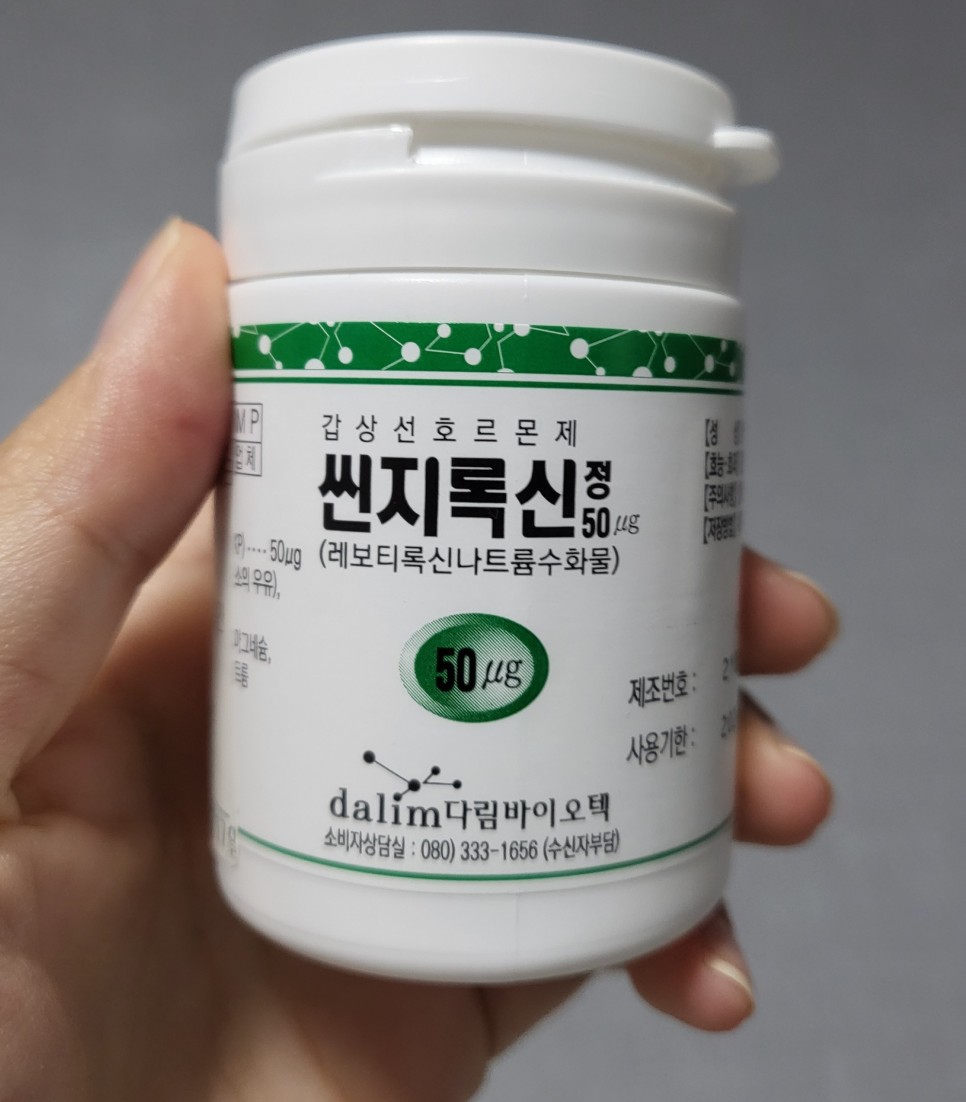

다행히 초음파 결과상 갑상샘의 모양에 이상이 있는 것은 아니었다.임신했다면 내 갑상샘호르몬이 태아에게 가서 갑상샘호르몬이 부족한 것 같은데.. 갑상샘호르몬은 태아발육에 지대한 영향을 미쳐 갑상샘호르몬약을 복용하는 것이 산모에게 부작용을 일으키지도 않는다.오히려 약을 먹지 않는 것이 태아에게는 매우 좋지 않다는 것.갑상선 수치를 걱정하는 임산부는 걱정하지 말고 약을 복용해 주시기 바랍니다!현재 14 주째인 저 역시 하루에 한 알을 꼬박꼬박 먹고 있습니다.

함유량이 다른 두 종류의 약을 처방받았고 며칠 뒤 검사 결과와 약 복용법을 문자로 다시 보내준다고 한다.

검사 결과가 나올 때까지는 산전검사 수치가 높았던 탓일까, 50마이크로그램?자리를 하루 한 알 먹으라고 했다.

이 알약들은 8주 시험에서 함량이 더 낮을 수도 있다. 이는 25마이크로그램이지만 반으로 나누어서 12.5마이크로그램이다.

그래도 작은 용량의 알약을 먹으라고 하네.

갑상샘약 복용법 갑상샘 호르몬은 새벽오전 분비가 모두 끝난다고 한다.오전 9시 이내에 빈속에 약을 복용하고 아침은 약 1시간 뒤부터 먹는 것이 좋다.